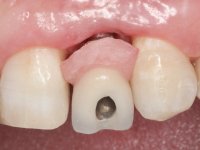

• Colocação de um Implante no local do dente 2.2. Reabilitação do implante com um “abutment” de componente coronário e gengival. em que o orifício de acesso ao parafuso fosse “camuflado” com uma faceta feldspática.

O tratamento iniciou-se com a re -preparação do coto do espigão falso coto fundido, com o objetivo de colocar as linhas de acabamento cervical com uma localização intra-sulcular e simultaneamente confecionar uma coroa provisória adaptada. Com um tratamento ortodôntico muito simples, fechou-se o diastema entre os incisivos centrais superiores e estabilizou-se esta posição com um arame colocado na superfície palatina dos centrais, funcionando como contenção. Posteriormente procurou-se fazer uma tração ortodôntica lenta do dente 2.2 com o intuito de diminuir, ainda que muito ligeiramente a perda óssea vertical nessa zona. Finalizada a tração, foi feita a extração do dente 2.2 e a zona foi reabilitada provisoriamente com uma coroa de resina composta colada aos dentes adjacentes. Foi colocado um implante dentário na zona do dente 2.2 sendo novamente colada a coroa provisória em resina, reabilitando provisoriamente a paciente durante o período de osseointegração. No dente 1.3 foi feita uma gengivectomia com bisturi elétrico, com a intenção de subir o nível cervical do 1.3 conseguindo uma maior harmonia com o dente 2.3. Estabilizados os tecidos moles, foi feita uma impressão com a técnica de moldeira aberta, utilizando silicones de adição de consistência “putty” e “light”. A recolha da cor, tanto da componente dentária como dos tecidos moles foi feita pelo ceramista no consultório.  No laboratório as impressões foram passadas a gesso e deram origem a modelos de trabalho que foram devidamente analisados. Foi decidido confecionar um “abutment” metalo-cerâmico aparafusado sobre o implante. Este “abutment” foi fundido com uma liga nobre e posteriormente revestido a cerâmica coronária e gengival. Dada a inclinação do implante o aparafusamento condicionou de forma inevitável a saída do orifício do parafuso pela superfície vestibular. No sentido de esconder esta situação, o desenho do “abutment” já foi idealizado com a intenção de acomodar na superfície vestibular a colagem de uma faceta feldspática. Este “abutment” foi provado em boca e foram feitos ajustes no componente cerâmico gengival. A sua adaptação aos tecidos moles foi feita tanto de forma subtrativa, com broca, como de forma aditiva, acrescentando resina composta de tonalidade gengival. Este acrescento de resina seria orientador do ceramista na colocação final da cerâmica de tonalidade gengival. A coroa que reabilitaria o dente 1.3 foi cimentada nesta consulta de prova com cimento de ionómero de vidro reforçado com resina composta. Finalizado o trabalho em laboratório da faceta sobre o 1.2 e o “abutment” e a faceta para o implante este foi colado em boca, após a colocação do isolamento absoluto. O trabalho satisfez plenamente a paciente. Durante oito anos a paciente foi seguida regularmente, mostrando-se agradada com o tratamento efetuado, no entanto começou a mostrar interesse em intervir esteticamente nos incisivos centrais superiores. Decidida a segunda fase da nossa intervenção, foi feita a preparação dentária dos dentes 1.1 e 2.1 para a colocação de duas facetas feldspáticas. Particular cuidado foi tido na preparação inter-proximal distal junto ao “abutment” do implante. Foi preciso avaliar muito pormenorizadamente o eixo de inserção da faceta em relação ao “abutment”. As facetas feldspáticas foram confecionadas em laboratório e posteriormente coladas em boca após a colocação de isolamento absoluto. Um ano após, iniciamos a nossa terceira fase de tratamento, após a faceta colada no dente 2.1 ter fraturado. A preparação dentária foi feita sobre a faceta colada, procurando estender mais para palatino o interface inter-proximal distal. O objetivo seria passar para mais palatino do ponto de contacto o interface faceta-dente. O preparo dentário do dente 1.2 também foi muito reduzido, limitando-se a criar um eixo de inserção. Após confecionadas a coroa total e a faceta em laboratório foram coladas em boca. Primeiro foi colada a coroa utilizando-se um isolamento relativo com teflon, posteriormente foi colada a faceta após a colocação do isolamento absoluto. Na coroa utilizei este tipo de isolamento para evitar a utilização de grampos. Seria difícil de aplicar pela forma e dimensão do dente e agressivo para os tecidos moles. Após a colagem foi avaliada a integração oclusal do trabalho.